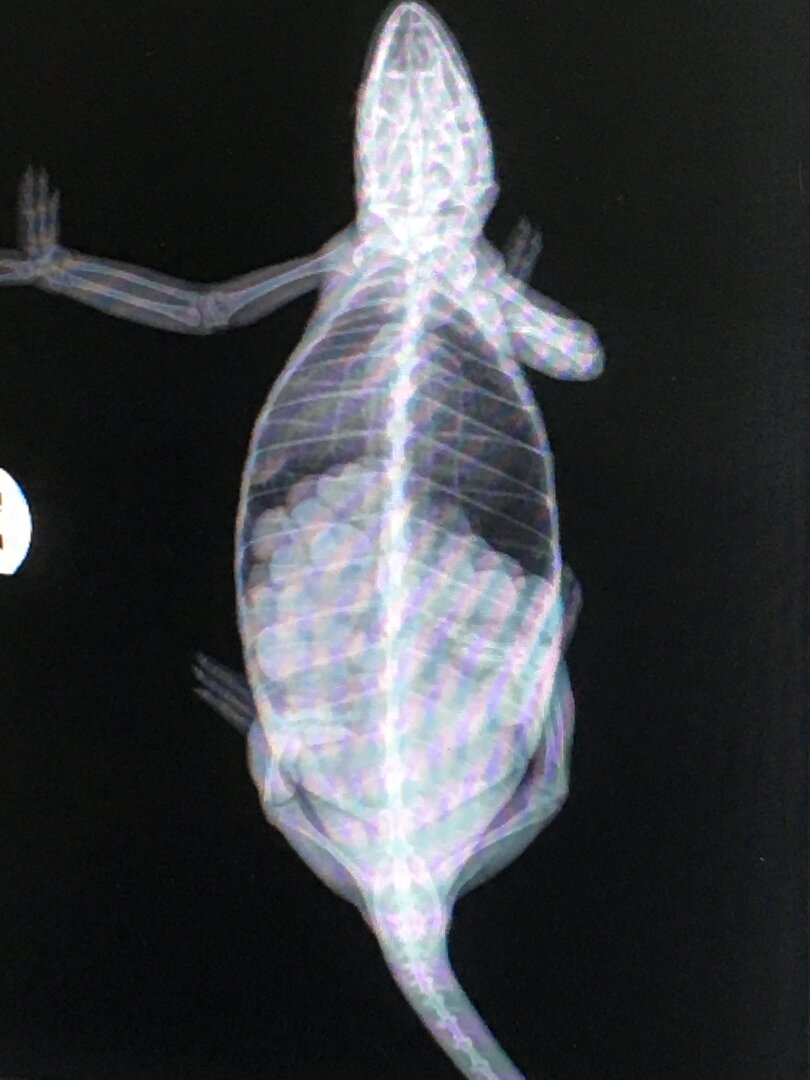

Our girl is about 6 months old and is bearing eggs (verified by X-Ray). Lost her appetite almost a month ago, and we are having to force feed her using Oxbow Carnivore Care/strained peas/calcium mixture. She used to eat 12-15 crickets per day plus one or two Superworms. We have her in a 48x24x24 mesh enclosure with a laying bin made of a 3-gallon bucket with sand/EcoEarth. We have both UVB and UVA bulbs going, plus an incandescent bulb by the laying bin. The cage is covered on all sides for privacy. She is not showing bumps/bulges on her flanks yet and has ignored the laying bin so far. Are we just too early or is she eggbound?

Are the eggs showing round or oval in the X-ray?

Not sure if they are round or oval judging from the x-ray. Maybe you can tell better than I.

I can't enlarge the photo big enough to be sure but they look more oval than round to me. She has a huge clutch. Sorry to tell you but that means you've been over feeding her. I hope she can lay them.